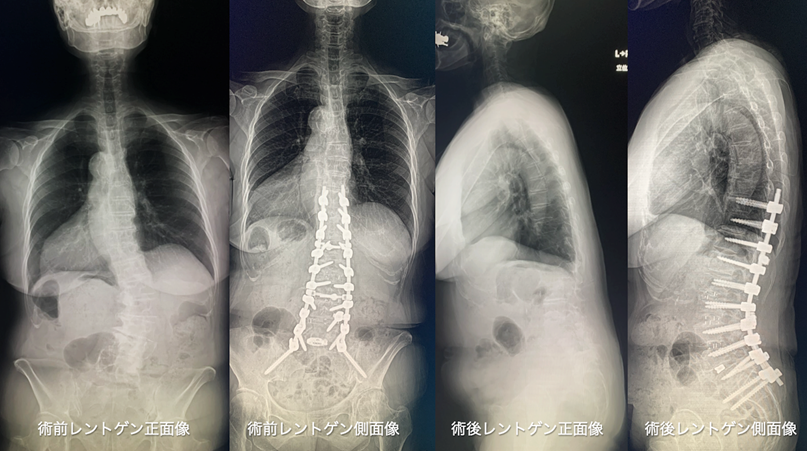

成人脊柱変形の患者様(70歳女性)

不良姿勢と立位保持、歩行維持困難あり。保存療法で改善しないために手術を行なった。手術は側方進入椎体間固定術を併用した2期的前後合併矯正固定術を行った。手術は2回とも4,5時間程度、自己血輸血で対応できたため、他人血の輸血は行わなかった。術後は姿勢・症状ともに改善した。

注)患者様の許可をいただき掲載しています